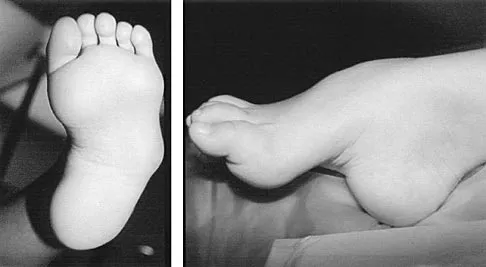

A 6-year-old girl has the bilateral foot deformity shown in Figure 1. There is no family history of disease. Examination reveals fixed hindfoot equinus, and muscle function testing shows strong posterior tibial function, fair plus anterior tibial function, poor peroneal function, and strong gastrocnemius function. A Coleman block test shows a correctable hindfoot. Nerve conduction velocity studies show diminished function in the peroneal and ulnar nerves on both sides. Pathologic changes found in a sural nerve biopsy include "onion bulb" formation, and DNA testing confirms the presence of a mutation in the MPZ gene, consistent with hereditary motor sensory neuropathy type III (HMSN-III). What is the best course of action?

Explanation

The patient has HMSN-III or Dejerine-Sottas syndrome. This form of HMSN progresses very rapidly and frequently results in severe foot deformity in early childhood. The changes are progressive and are the result of muscle imbalance during growth. Balancing of the foot musculature is essential, particularly during the phases of rapid growth of the foot. However, this cannot be accomplished using the anterior tibial muscle because it is already weak and the transfer will further weaken it. Bony procedures also may be required, and tendon transfers cannot be depended on to correct bony deformity. However, these procedures can be deferred until the foot is closer to adult size. Surgeries that lead to joint arthrodesis, such as triple arthrodesis and some midfoot osteotomies, are contraindicated because the feet may lose protective sensation as the disease progresses. Fusions in insensate feet are less successful than realignment procedures that maintain mobility. Wetmore RS, Drennan JC: Long-term results of triple arthrodesis in Charcot-Marie-Tooth disease. J Bone Joint Surg Am 1989;71:417-422. Roper BA, Tibrewal SB: Soft tissue surgery in Charcot-Marie-Tooth. J Bone Joint Surg Br 1989;71:17-20.